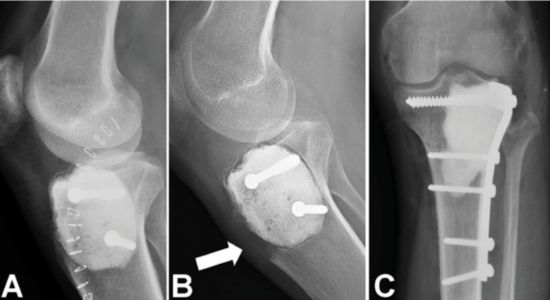

Figura 3. A) Radiografia pós-operatória imediata do joelho após curetagem de um TCGP (tumor de células gigantes do osso) na tíbia proximal; o cimento é visível preenchendo o defeito. B) Após 18 meses, houve recidiva local com osteólise severa adjacente ao cimento e ruptura do osso cortical. C) Radiografia anteroposterior mostrando o tratamento cirúrgico da recidiva (curetagem, perfuração, fulguração e alcoolização com etanol a 99%) com preservação articular bem-sucedida. Foram utilizados cimento ósseo e reforço com uma placa proximal da tíbia.

Figura 3. A) Radiografia pós-operatória imediata do joelho após curetagem de um TCGP (tumor de células gigantes do osso) na tíbia proximal; o cimento é visível preenchendo o defeito. B) Após 18 meses, houve recidiva local com osteólise severa adjacente ao cimento e ruptura do osso cortical. C) Radiografia anteroposterior mostrando o tratamento cirúrgico da recidiva (curetagem, perfuração, fulguração e alcoolização com etanol a 99%) com preservação articular bem-sucedida. Foram utilizados cimento ósseo e reforço com uma placa proximal da tíbia.